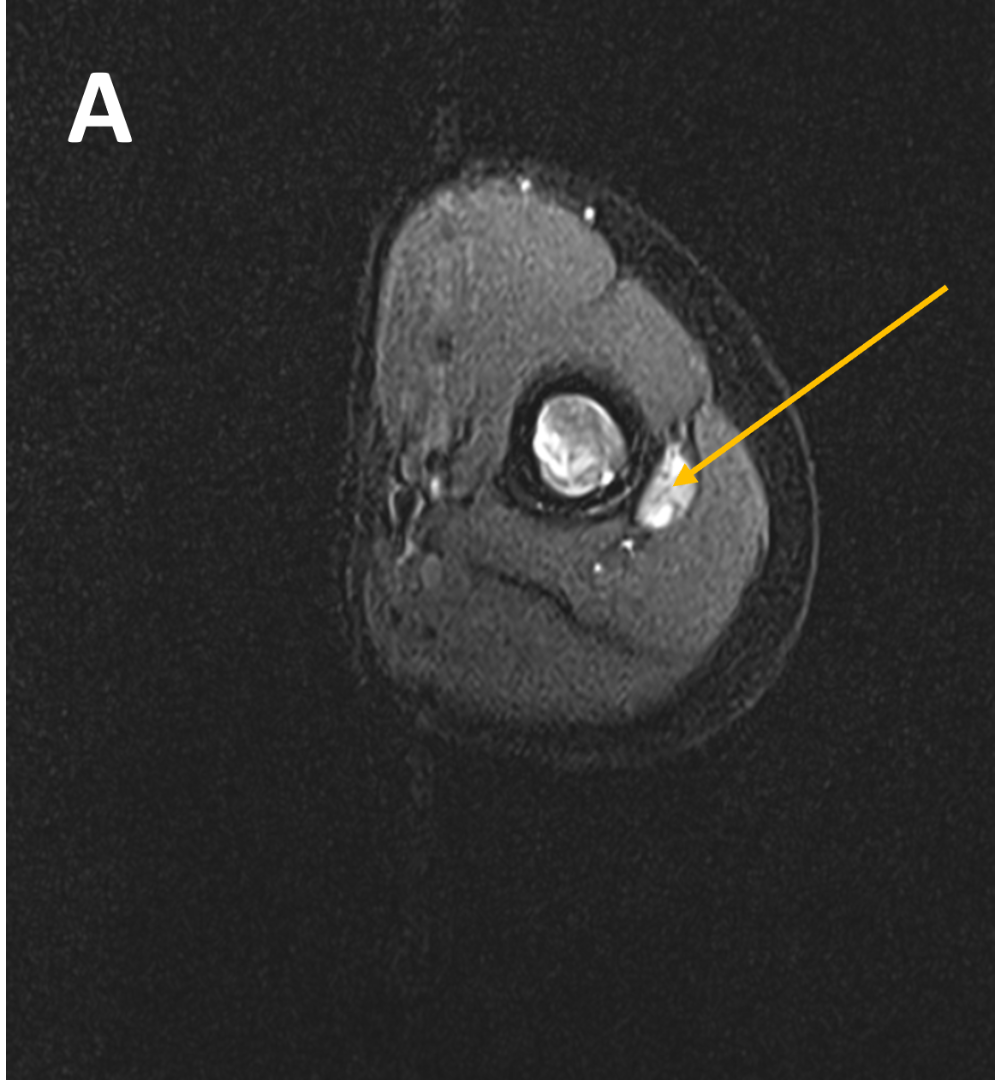

- (A,B) : MR LEFT FOREARM

- A : MR LEFT FOREARM : Fusiform thickening of radial nerve in the posterior compartments of mid-distal 1/3rd arm, as its winds around the spiral groove of the humerus, before piercing the lateral intermuscular septum.